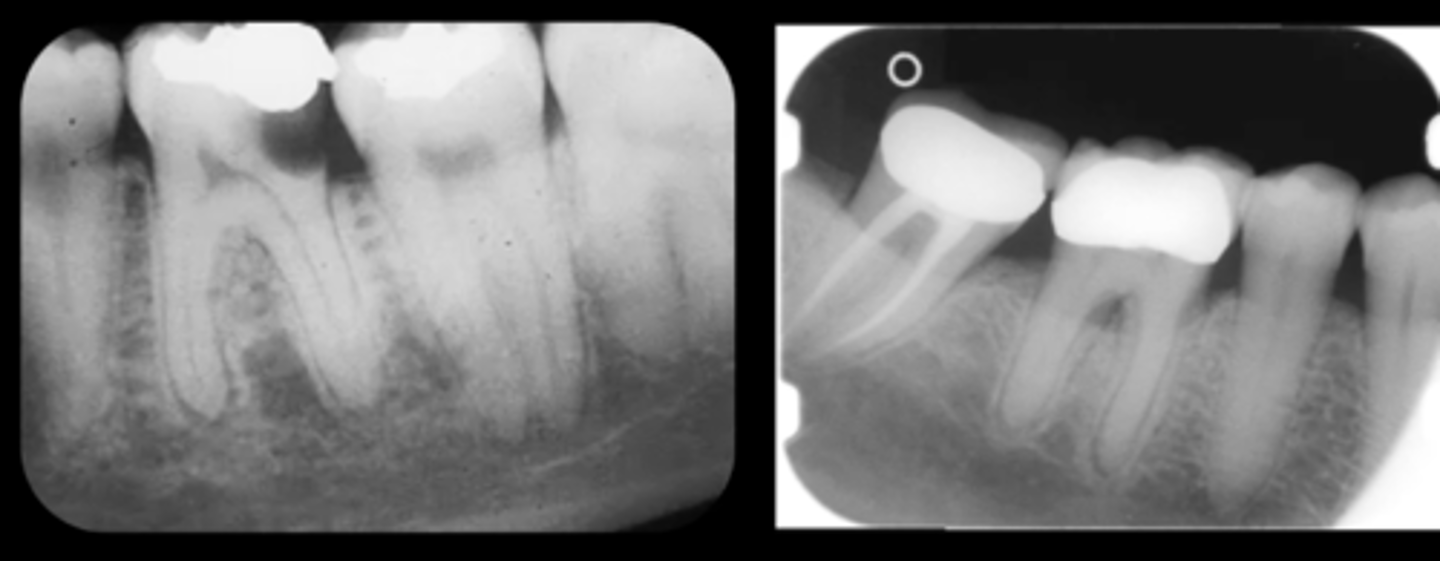

Example of a periapical x-ray:

What anatomy is demonstrated in periapical imaging? What kind of information?

• Provides detailed information about the teeth and the surrounding alveolar bone

• Demonstrates crown to apex.

• At least 2mm bone, ideally 5mm beyond apex.

What are the clinical indications for periapical imaging? List some.

• Apical infection/inflammation

• Peridontal status

• Trauma to the teeth and alveolar bone

• Assessment of unerupted teeth

• Assessment of roof morphology

• Pre treatment

• During endodontics

• Post treatment

• Detail on apical cysts and lesions